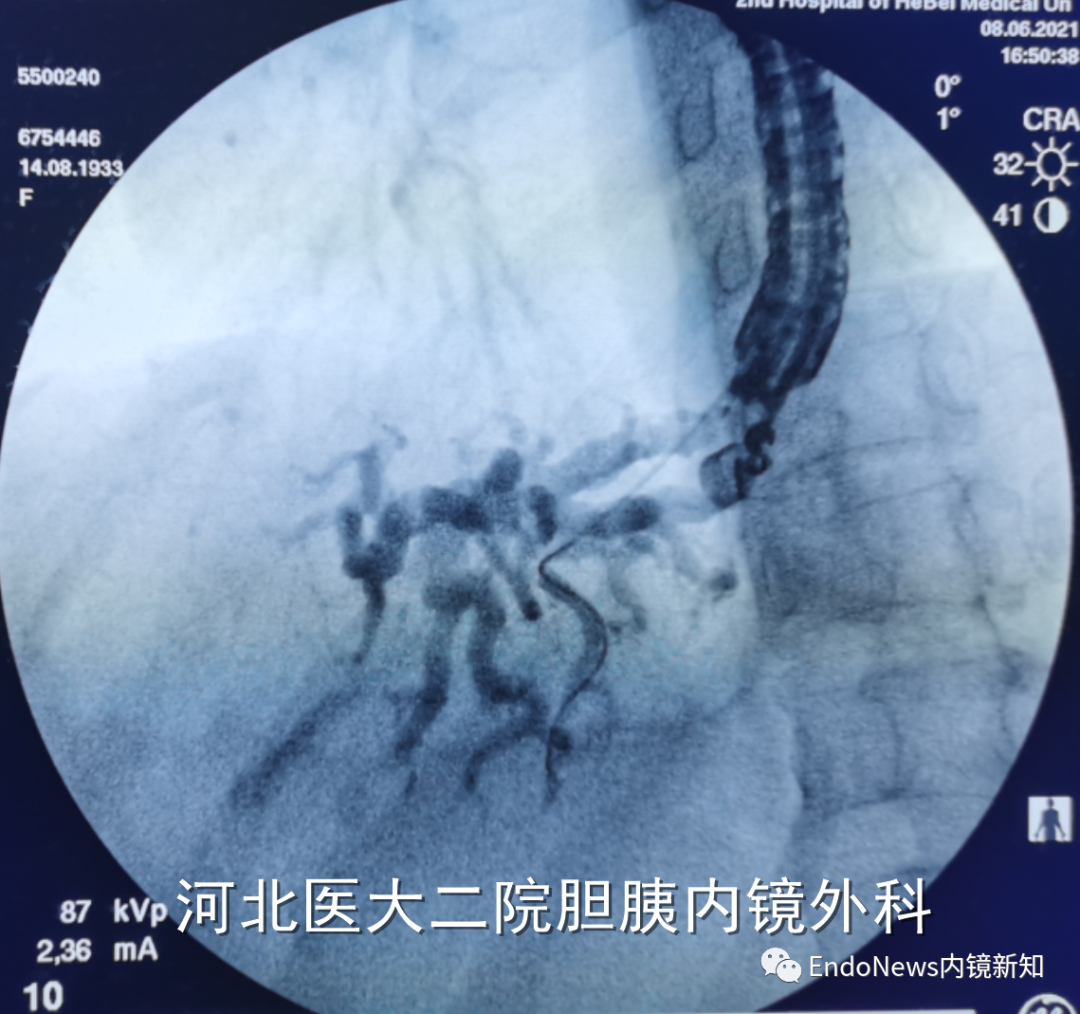

行经十二指肠胆管穿刺(CDS)时一般不需要考虑以上问题,但如因某些特殊原因涉及到会师操作时可能涉及到导丝自胆总管上游朝向下游的超选。一般情况下,CDS的时候穿刺针的方向是朝向肝内的,比如下图:

如果这个时候放支架行CDS就可以结束手术了,如果需要做顺行或者会师,就需要使导丝返折180°朝向胆管下游方向穿出十二指肠乳头。